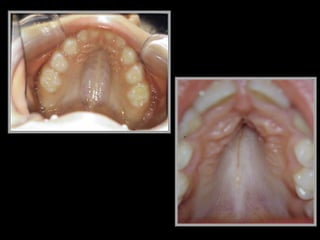

1) Alteração da formação da boca e

dentes

1) Alteração daformação da boca e dentes 2) Alteração dos seios da face  sinusite 3) Alergias: de pele asma 4) Alterações do nariz e ouvido – otite – rinite – desvio de septo

SÃO ALTERAÇÕES QUEOCORREM TRIDIMENSIONALMENTE